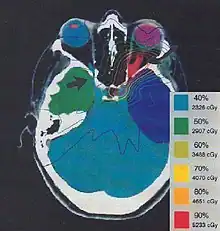

The more formal optimization process is typically referred to as forward planning and inverse planning.[12][13] Plans are often assessed with the aid of dose-volume histograms, allowing the clinician to evaluate the uniformity of the dose to the diseased tissue (tumor) and sparing of healthy structures.

Treatment plan for an Optic nerve sheath meningioma